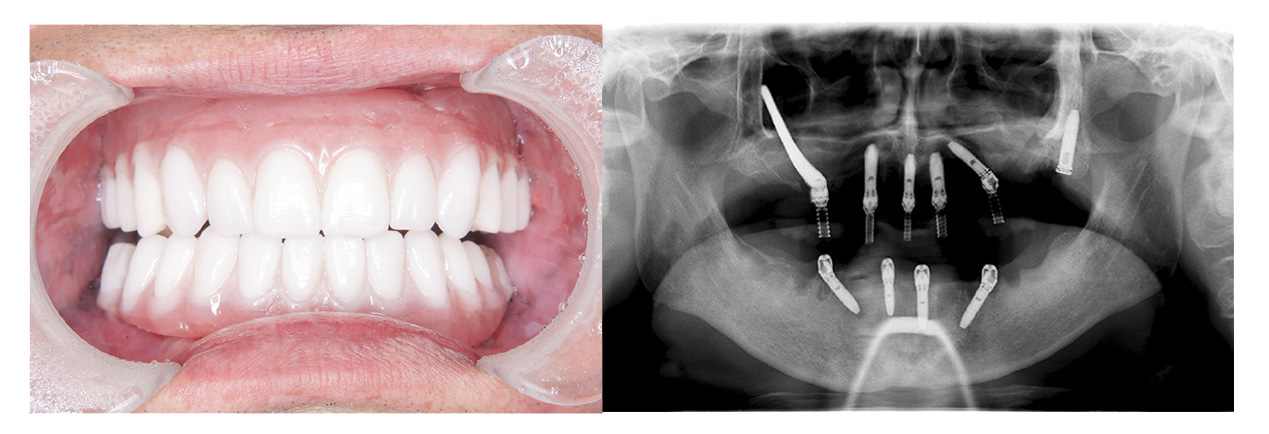

症例その3オールオン4

• Before

• After

咀嚼、審美障害。歯周病でグラグラな歯を全部抜歯してオールオン4で治療した症例。